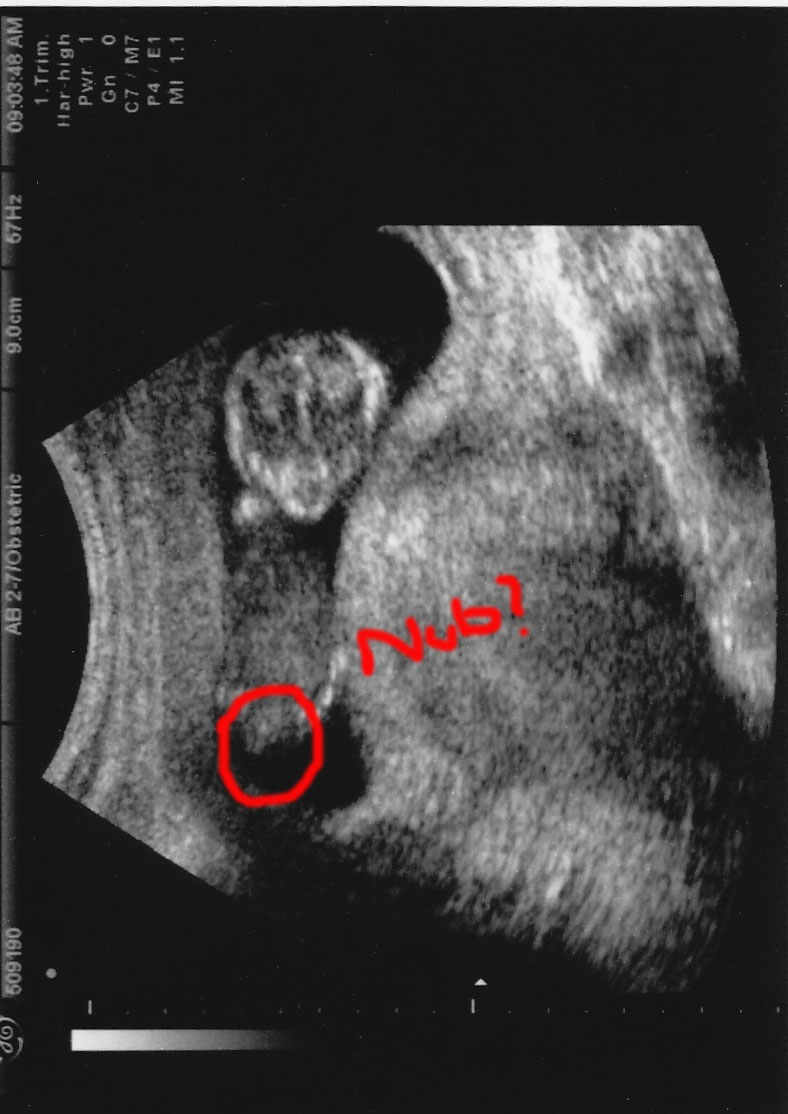

Well I had my 12 week scan today and ALL the pictures given to me were head on of the baby's face. Then I was just looking at them and I noticed this one. Not even sure if this a the profile of the baby, and I flipped it too. Well let me know what you think.

Attachment 10546